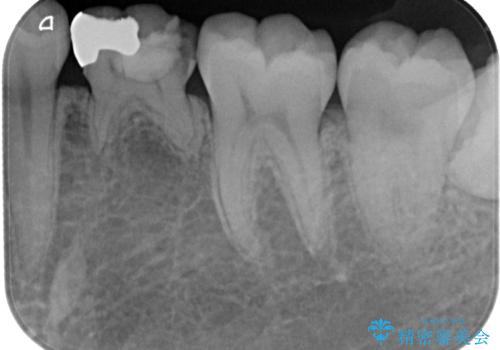

レントゲン上で金属の詰め物(メタルインレー)の下に虫歯を認めた為、オールセラミッククラウンでの治療と、乳歯なので予後を考えインプラントによる補綴治療もご提案しましたが、患者様の強い希望によりオールセラミッククラウンでの治療となりました。

拡大鏡視野下で、金属の詰め物(メタルインレー)、虫歯の除去を行い、オールセラミッククラウンに適した形に整えました。